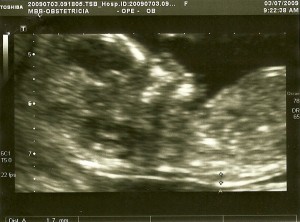

Hoje foi  a primeira oportunidade do Fernando me acompanhar à consulta.

Primeiro fizemos a ecografia e depois fomos à consulta com o obstetra e a enfermeira e depois fui fazer o rastreio bioquímico, uma análise de sangue que permite juntamente com outros exames de diagnóstico pré-natal calcular o risco da ocorrência de algumas patologias. A patologia mais divulgada de entre as possíveis de despistar é o Sindrome de Down (trissomia 21), que é a mais conhecida pela sua frequência e relevância em termos sociais.

Foi emocionante ver o nosso pequeno feto com 12 semanas e 5 dias a flectir e esticar as pernas, a mexer a mão e a abrir e fechar a boca! Conseguimos contar os dedos das mãos, ver os rins e a bexiga, ver e ouvir o coração a bater, enfim…

É um momento em que nos apercebemos que é real, existe mesmo um pequeno ser dentro de mim! E que tem de ser protegido porque é muito frágil!

As imagens do nosso bebé a movimentar-se dentro do meu útero é uma imagem que não me sai da cabeça e da do Fernando! Lindo! Ainda bem que temos toda esta tecnologia à nossa disposição!

O vínculo entre a tríade (mãe/pai/filho) já está em formação!

eco12s+5d

2eco12s5d